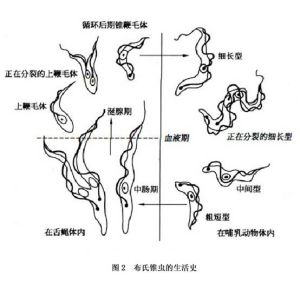

布氏錐蟲生活史

布氏錐蟲生活史布氏錐蟲病是由布氏錐蟲指名亞種(Trypanosoma brucei Brucei)引起的,在形態上與岡比錐蟲和羅得西亞錐蟲形態相似。過去一直視為獨立的3個種。後經Hoare(1967)等學者論證,認為這3種均屬布氏錐蟲一個種。岡比錐蟲和羅得西亞錐蟲均屬布氏錐蟲的亞種。但它們感染的宿主和發病的症狀有所不同。布氏錐蟲指名亞種引起的動物的錐蟲病。岡比錐蟲種和羅得西亞錐蟲引起人的非洲錐蟲病(睡覺病)。

布氏錐蟲在自然感染的脊椎動物宿主體內是一種多形的蟲體,在血液中可見到沒有鞭毛的短粗型和具有鞭毛的細長型以及過渡型。因此蟲體的大小不一致,長度介於12~35um,寬度介於1.5~3.5um、錐蟲體扁無色。體形似葉,前端逐漸變為細尖,後端較圓。在體中部或中部附近,有1較大的核;近後端有1扁圓形的動基體。蟲體的一側有寬而呈波浪狀的波動膜,有1根鞭毛自毛基體發出,沿波動膜的邊緣向前延伸,在前端伸出,成游離的鞭毛。錐蟲很活潑,借鞭毛和波動膜運動。錐蟲借縱分裂繁殖,在塗片檢查時可見到正在分裂的蟲體。

生活史

采采蠅

采采蠅布氏錐蟲的傳播媒介是舌蠅屬中的多種舌蠅。舌蠅又稱采采蠅。舌蠅屬中的刺舌蠅、須舌蠅、白色舌蠅是主要的傳播媒介,其他如長翅舌蠅、有飾舌蠅和似寄舌蠅等也能傳播布氏錐蟲病。當采采蠅叮咬病畜的血液時,錐蟲被吸入蠅體,先在消化道內,後至唾液腺內,其間經過2~3周複雜的周期性發育繁殖,經過短膜型至後錐型或後循環錐蟲型。後循環錐蟲是感染期蟲體,它們大量地積聚於唾液腺中。當采采蠅再次吸血時,後循環錐蟲隨同采采蠅唾液注入動物體內,使之遭受感染。從采采蠅吸入含錐蟲的血液發育至具感染性的後循環錐蟲需經過一定的時間,在刺舌蠅至少需11天,在須舌蠅至少為15~18天。除采采蠅之外,其它吸血昆蟲也可能機械性地傳播此病,即通過這些吸血昆蟲刺患病家畜血液的數小時內,由污染的口器而傳播給另外的家畜。也曾有先天性感染和通過性交而傳染本病的報導。